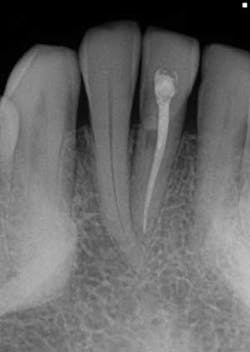

- In Figure 8, the lesion is advanced significantly (one-and-a-half years had gone by) the irregular borders and moth-eaten appearance is easily observed.

- Definitive diagnosis: external resorption.